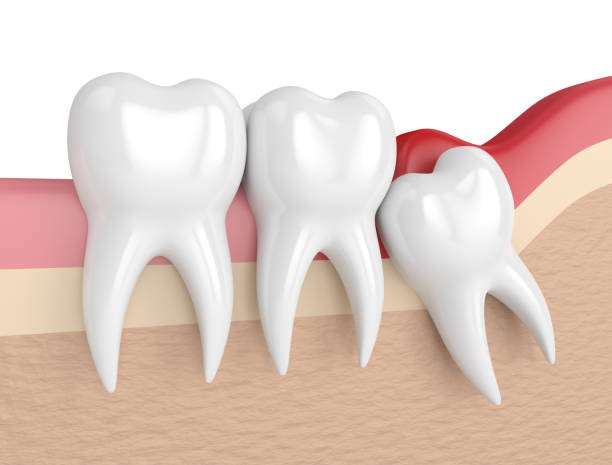

ថ្គាមទាល់ដែលរងផលប៉ះពាល់

ប្រសិនបើថ្គាមទាល់របស់អ្នកលូតលាស់មិនត្រឹមត្រូវ វានឹងបង្កឱ្យមានផលប៉ះពាល់ដល់រាងកាយ ព្រោះវាអាចនឹងមិនមានកន្លែងដុះគ្រប់គ្រាន់នៅក្នុងមាត់អ្នក ដែលអាចបណ្តាលឱ្យ៖

- លេចសាច់ប៉ោងឡើងនៅក្នុងមាត់

- ជាប់គាំងនៅក្នុងថ្គាម

- ប៉ះពាល់ដល់ថ្គាមផ្សេងទៀត

នៅពេលដែលថ្គាមទាល់ដុះចូលទៅក្នុងមាត់ដែលមិនមានកន្លែងគ្រប់គ្រាន់សម្រាប់ពួកគេ វាអាចបណ្តាលឱ្យធ្មេញផ្សេងទៀតផ្លាស់ប្ដូរឬរង្គើ ដែលបណ្តាលឱ្យមានការខាំមិនត្រឹមត្រូវ។ ការខាំមិនត្រឹមត្រូវអាចធ្វើឱ្យថ្គាមក្រោមរបស់អ្នករង្គើក ហើយវាអាចបណ្តាលឱ្យមានការឈឺចាប់ រួមទាំងឈឺក្បាលផងដែរ។